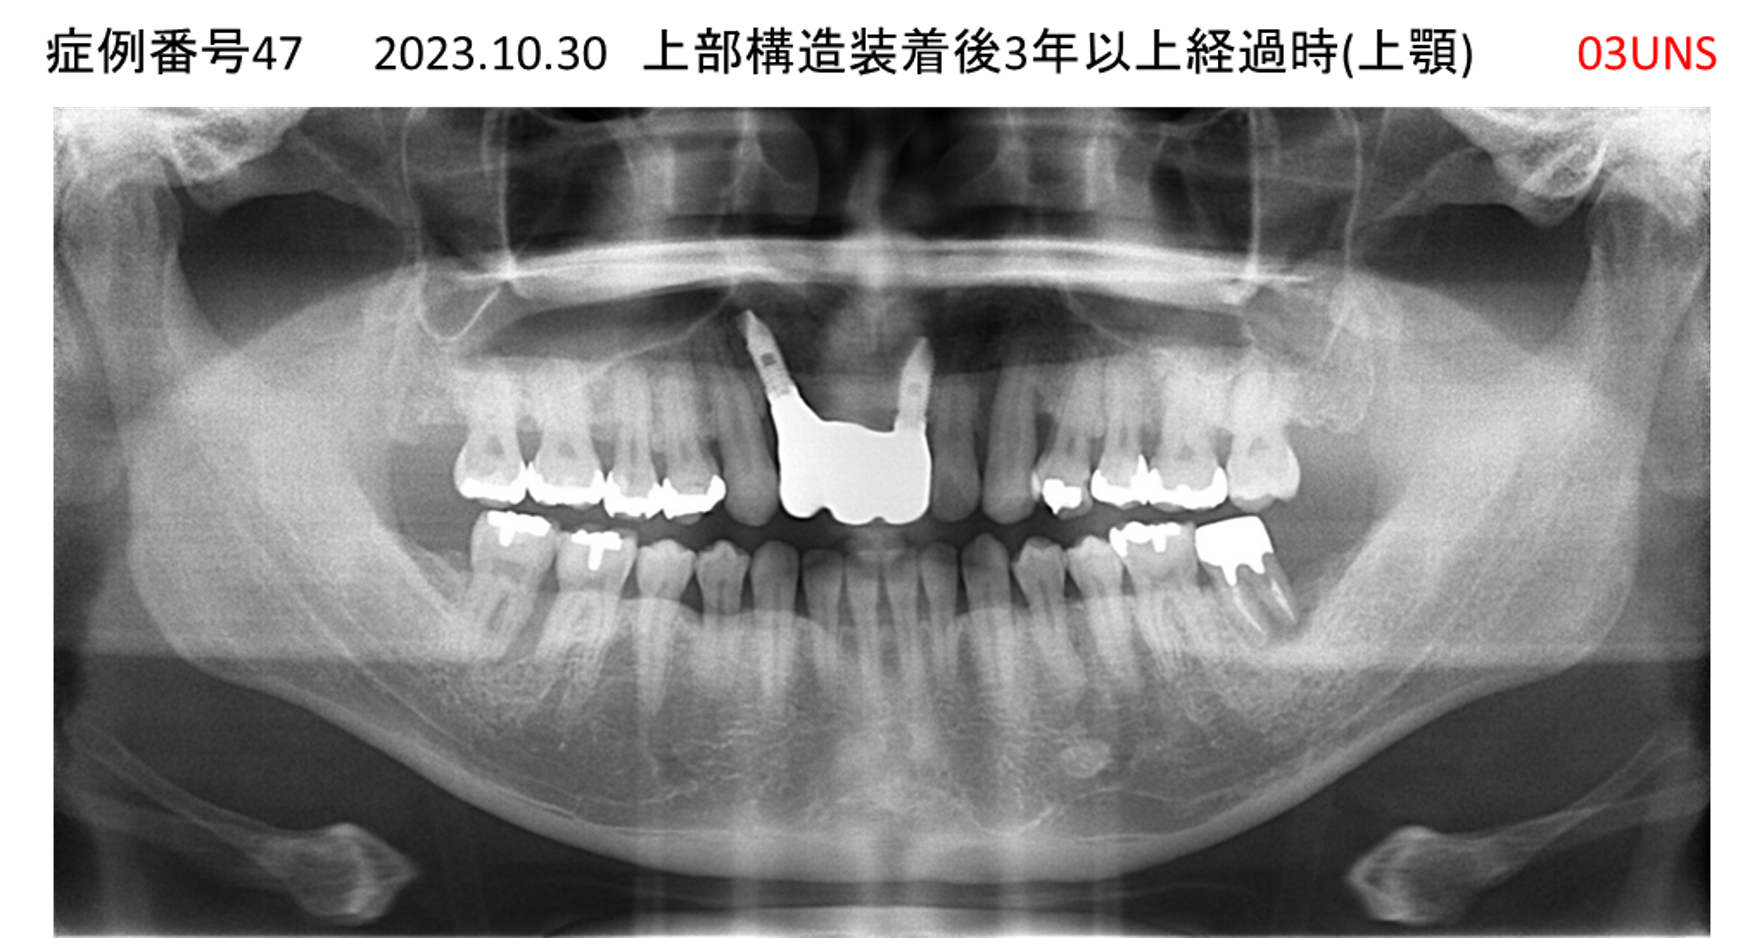

上の前歯が揺れてきてかめない患者様のインプラント症例

| 治療名称 |

インプラント |

| 治療費用 |

440万円+税 |

| 治療期間 |

6か月 |

| 患者さんの症状(主訴) |

上の前歯が揺れてきた。かめない |

| 治療内容 |

サイナスリフト、GBR、インプラント、即時荷重 |

| 治療結果 |

上の前歯の揺れが収まった。奥歯でしっかり噛める。 |

| 治療の注意点(リスク/副作用) |

インプラントが壊れたら再治療が必要 |